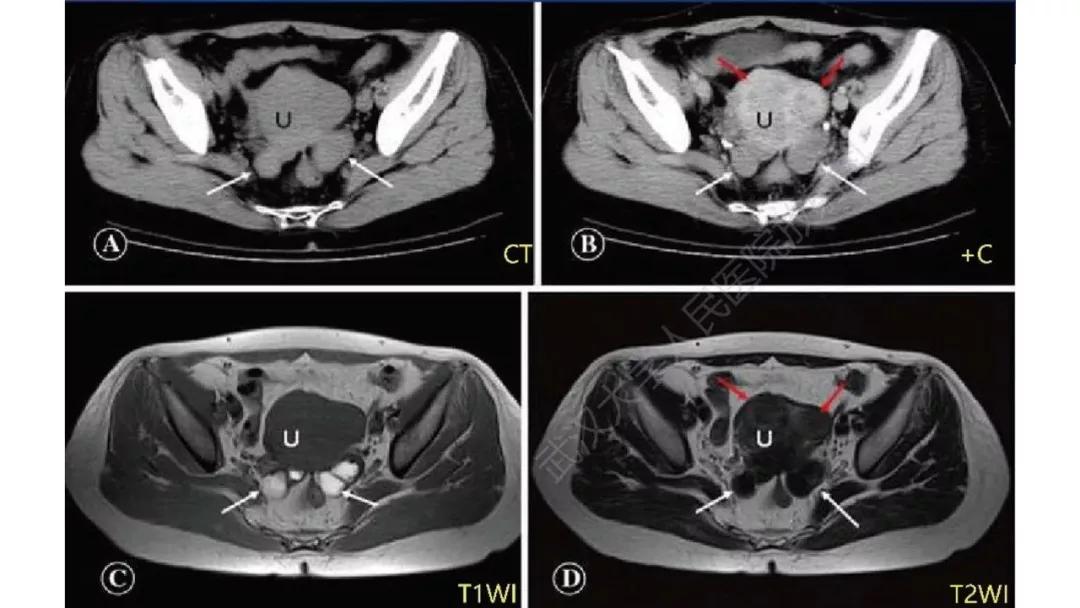

病理:颗粒细胞瘤